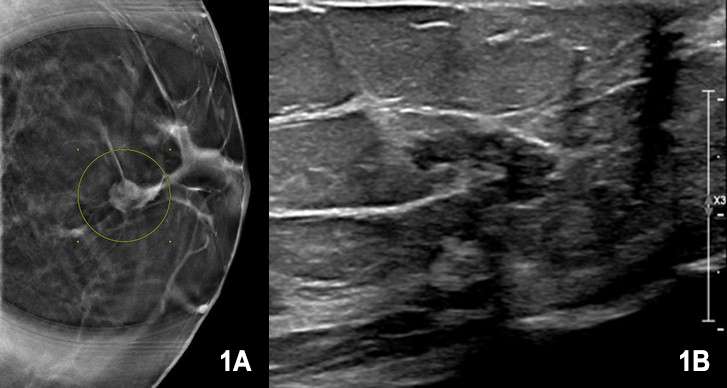

No definite sonographic or mammographic features can be used to reliably distinguish the different subtypes of papillary carcinoma. Mammographically, they often present as large, well defined, lobulated masses. On ultrasound, they are usually hypoechoic, solid and cystic masses with or without associated posterior acoustic enhancement.6 On MRI, they usually present as enhancing complex cystic or multicystic lesions with a solid central component; the solid component can show either homogeneous or heterogeneous enhancement. 7

Case 1